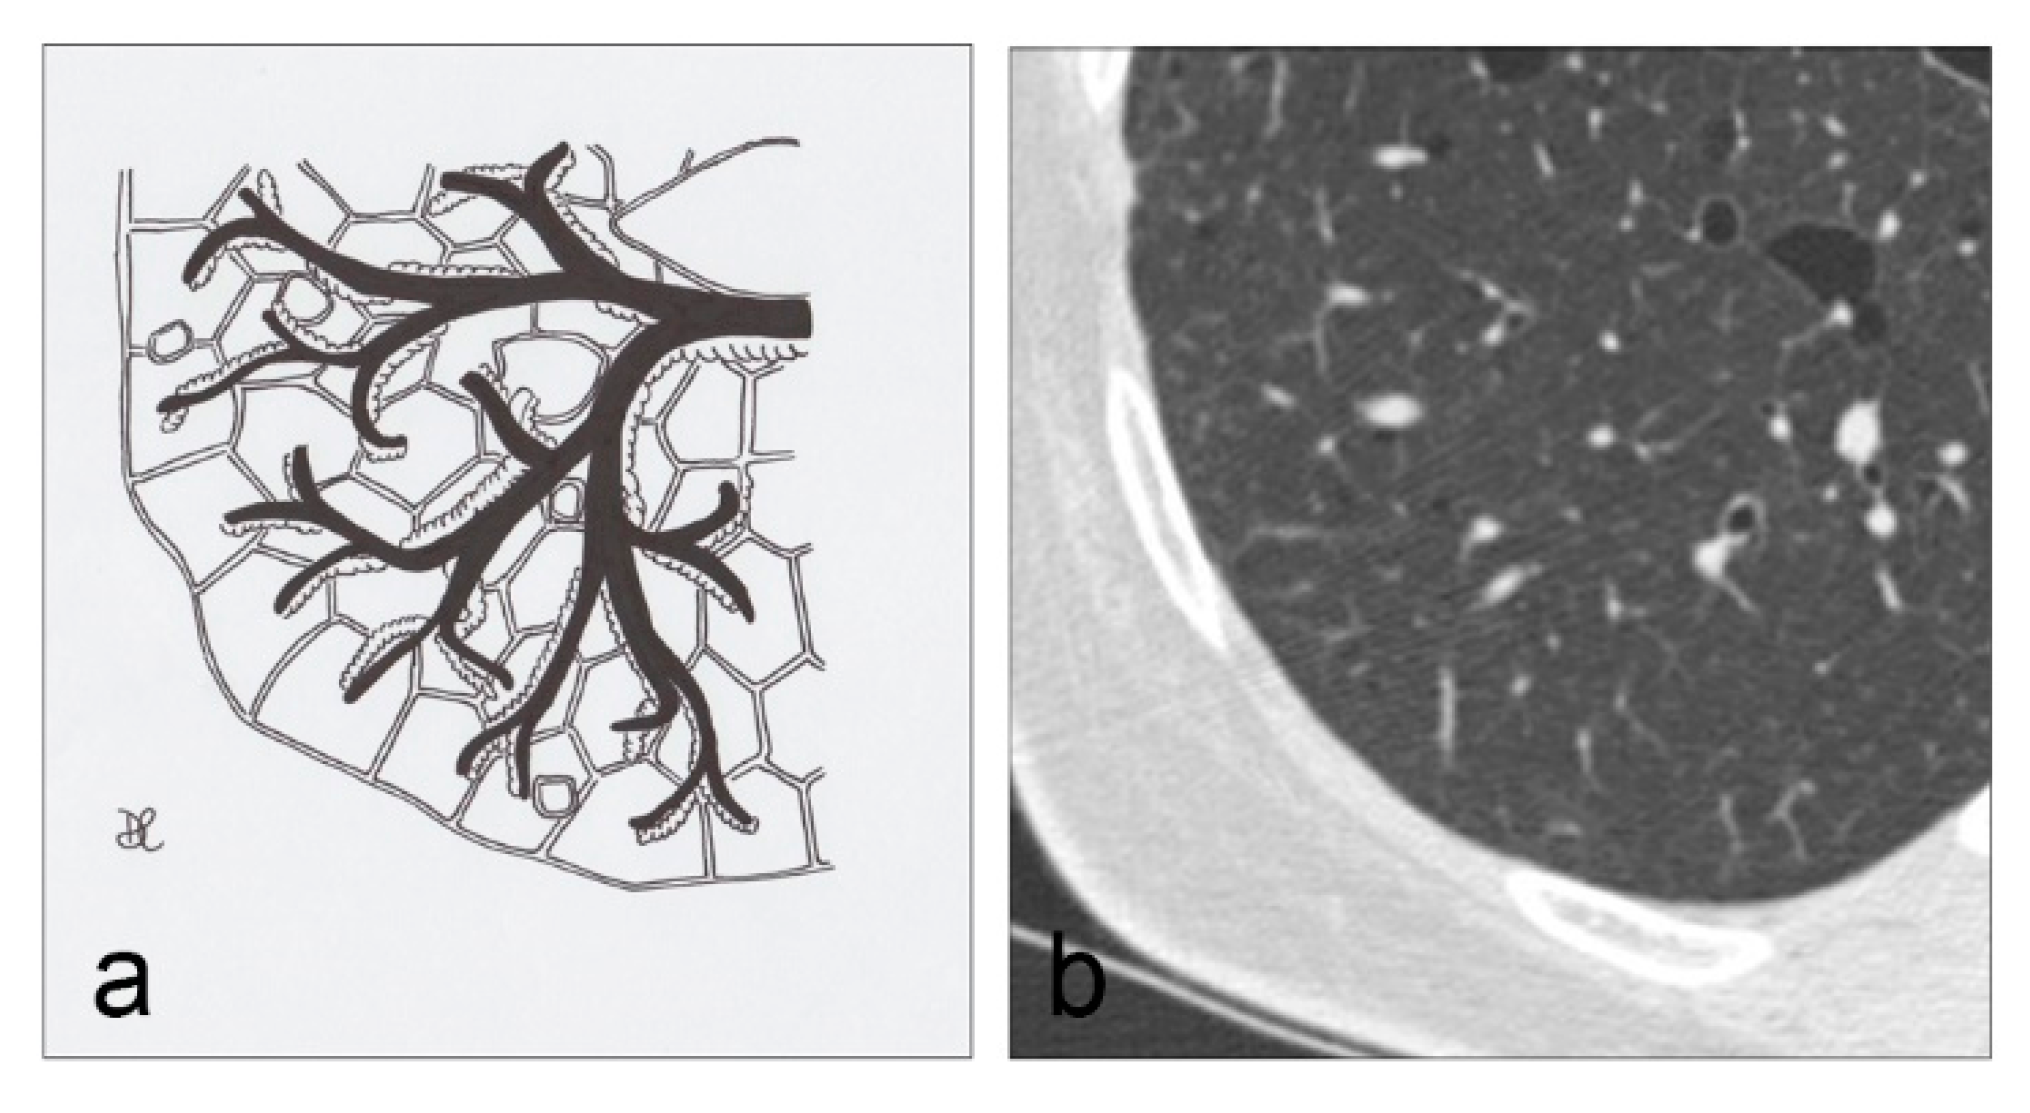

Figure 12. In NF1, the cysts usually present no clearly-defined walls. These lesions are predominant in the superior regions (a,b). Detail of NF1 cysts (b).

On chest radiographs, a reticular pattern with Kerley’s B lines may be observed in 50% of cases, associated with a typical lung volume increase; on HRCT scans, diffused and irregular shaped lung cysts or bullae can be rarely appreciated, predominantly distributed in upper lobes (Figure 12 and Figure 13), having symmetric location, with a significant risk of pneumothorax [46]; in addition to cysts, basilar bilateral reticulation, “ground glass” opacities and emphysema are often detected in these patients. Other thoracic alterations include cutaneous, subcutaneous and intercostal neurofibromas, “ribbon” ribs, thoracic meningoceles, paraganglioma, pheochromocytoma, intestinal carcinoids, mediastinal masses and pulmonary fibrosis [47].